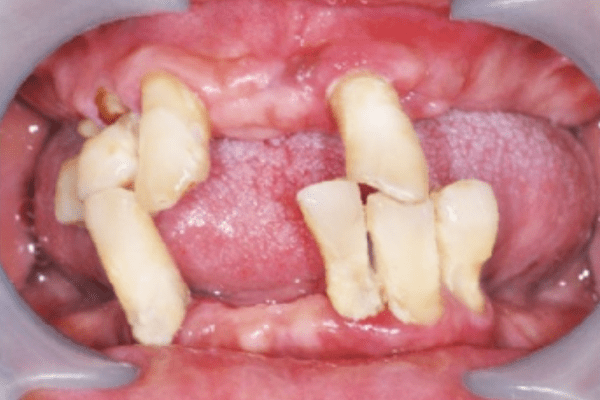

術前照-口腔(周先生)